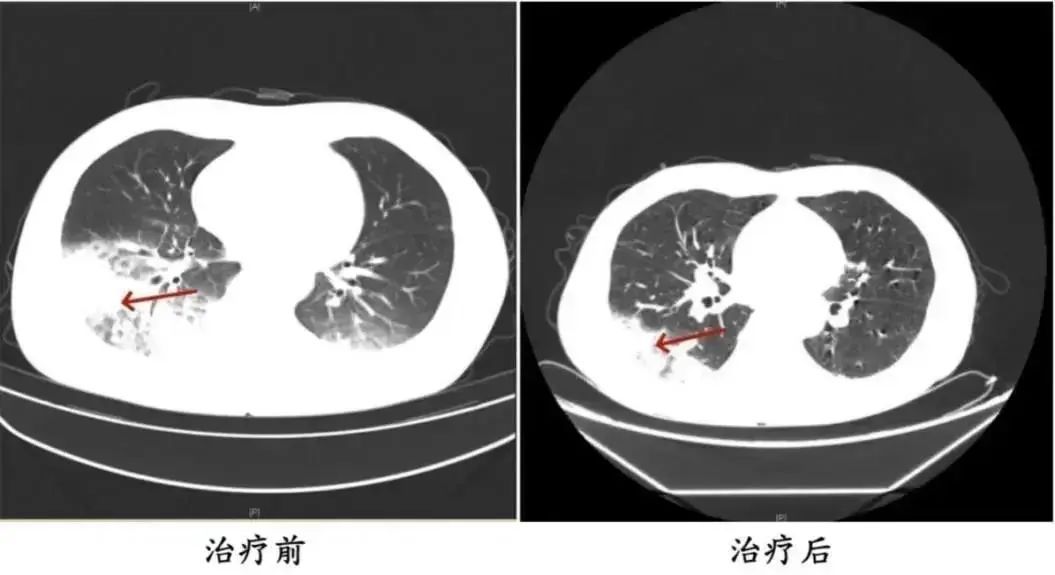

△周先生治疗前后的肺部CT影像

经诊断,患者感染了军团菌肺炎